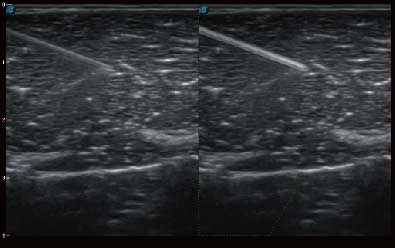

微米成像技术提升了对组织斑点噪声信号的抑制能力,并进一步强化边界信息,从而获得清晰图像。

自动识别穿刺针进行声束智能偏转 手动修正多档调节 提高一次穿刺成功率

自动识别组织边界信息进行图像无损拼接 抖动抑制技术提高成像效果 完整显示较大病灶及组织,为临床提供可靠诊疗方案